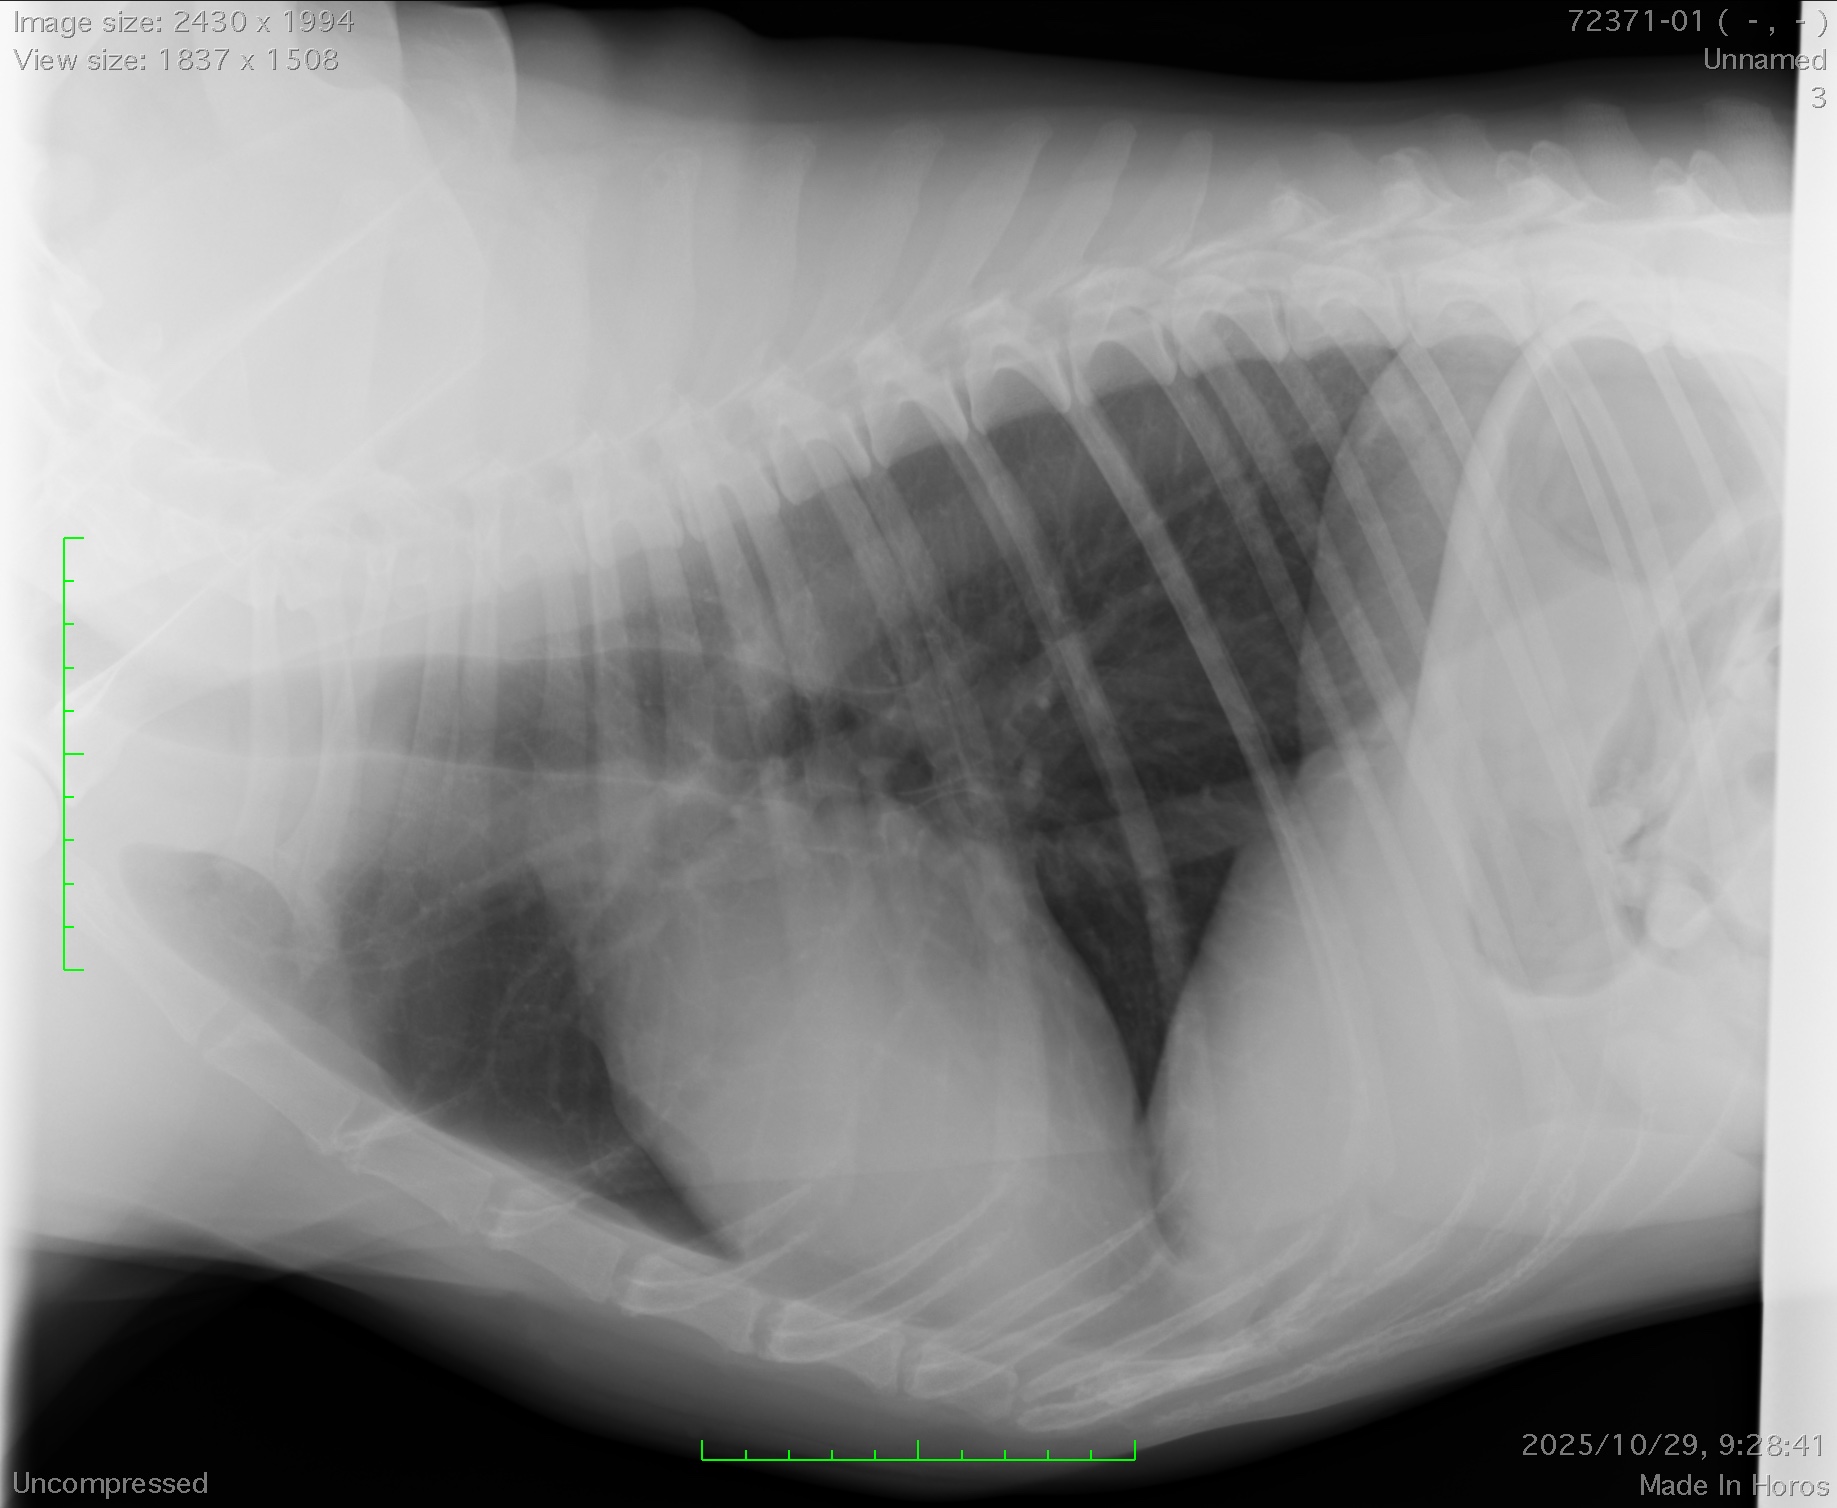

今回は2時間程度の手術で、無事に腫瘍は摘出され、本人の状態もとても良かったため、翌日に帰宅となりました。術後のX線で腫瘍がきれいになくなっているのが分かると思います。胸腺腫は摘出が完全に実施されると比較的予後が良いと言われています。今回の手術でわんちゃんが元気で長生きできることを願っております